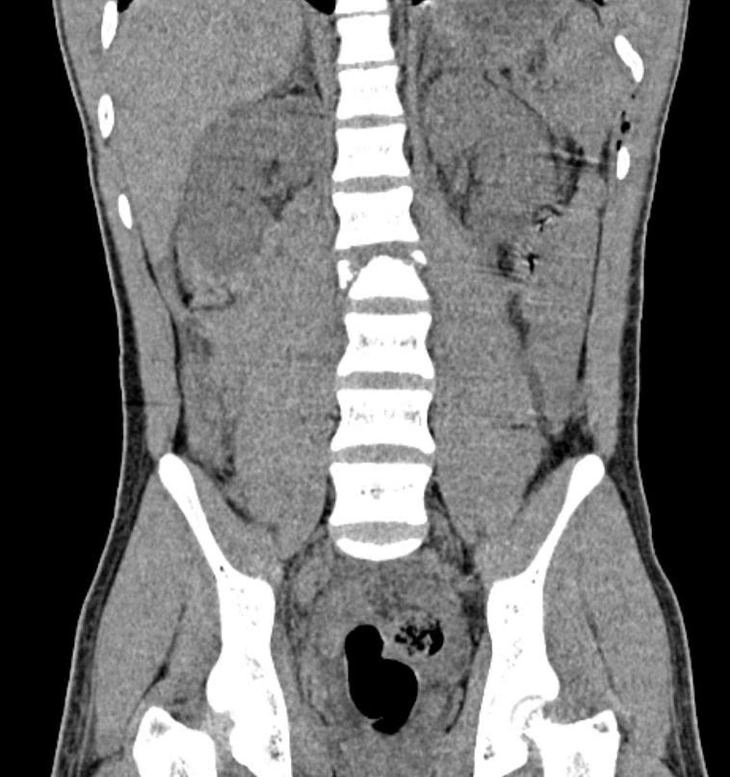

Hình ảnh chụp cắt lớp cho thấy bệnh nhi bị gãy xẹp đốt sống L2 - Ảnh: Bệnh viện cung cấp

Tại một bệnh viện địa phương, các kết quả chẩn đoán hình ảnh cho thấy em bị gãy xương sống, tủy bị đứt, xương sống gãy vỡ phức tạp, nên được chuyển khẩn vào Bệnh viện Nhi đồng 2. Ê kíp phẫu thuật đã nhanh chóng đặt dụng cụ cố định cột sống, giúp em giảm đau và tránh lở loét do nằm lâu.